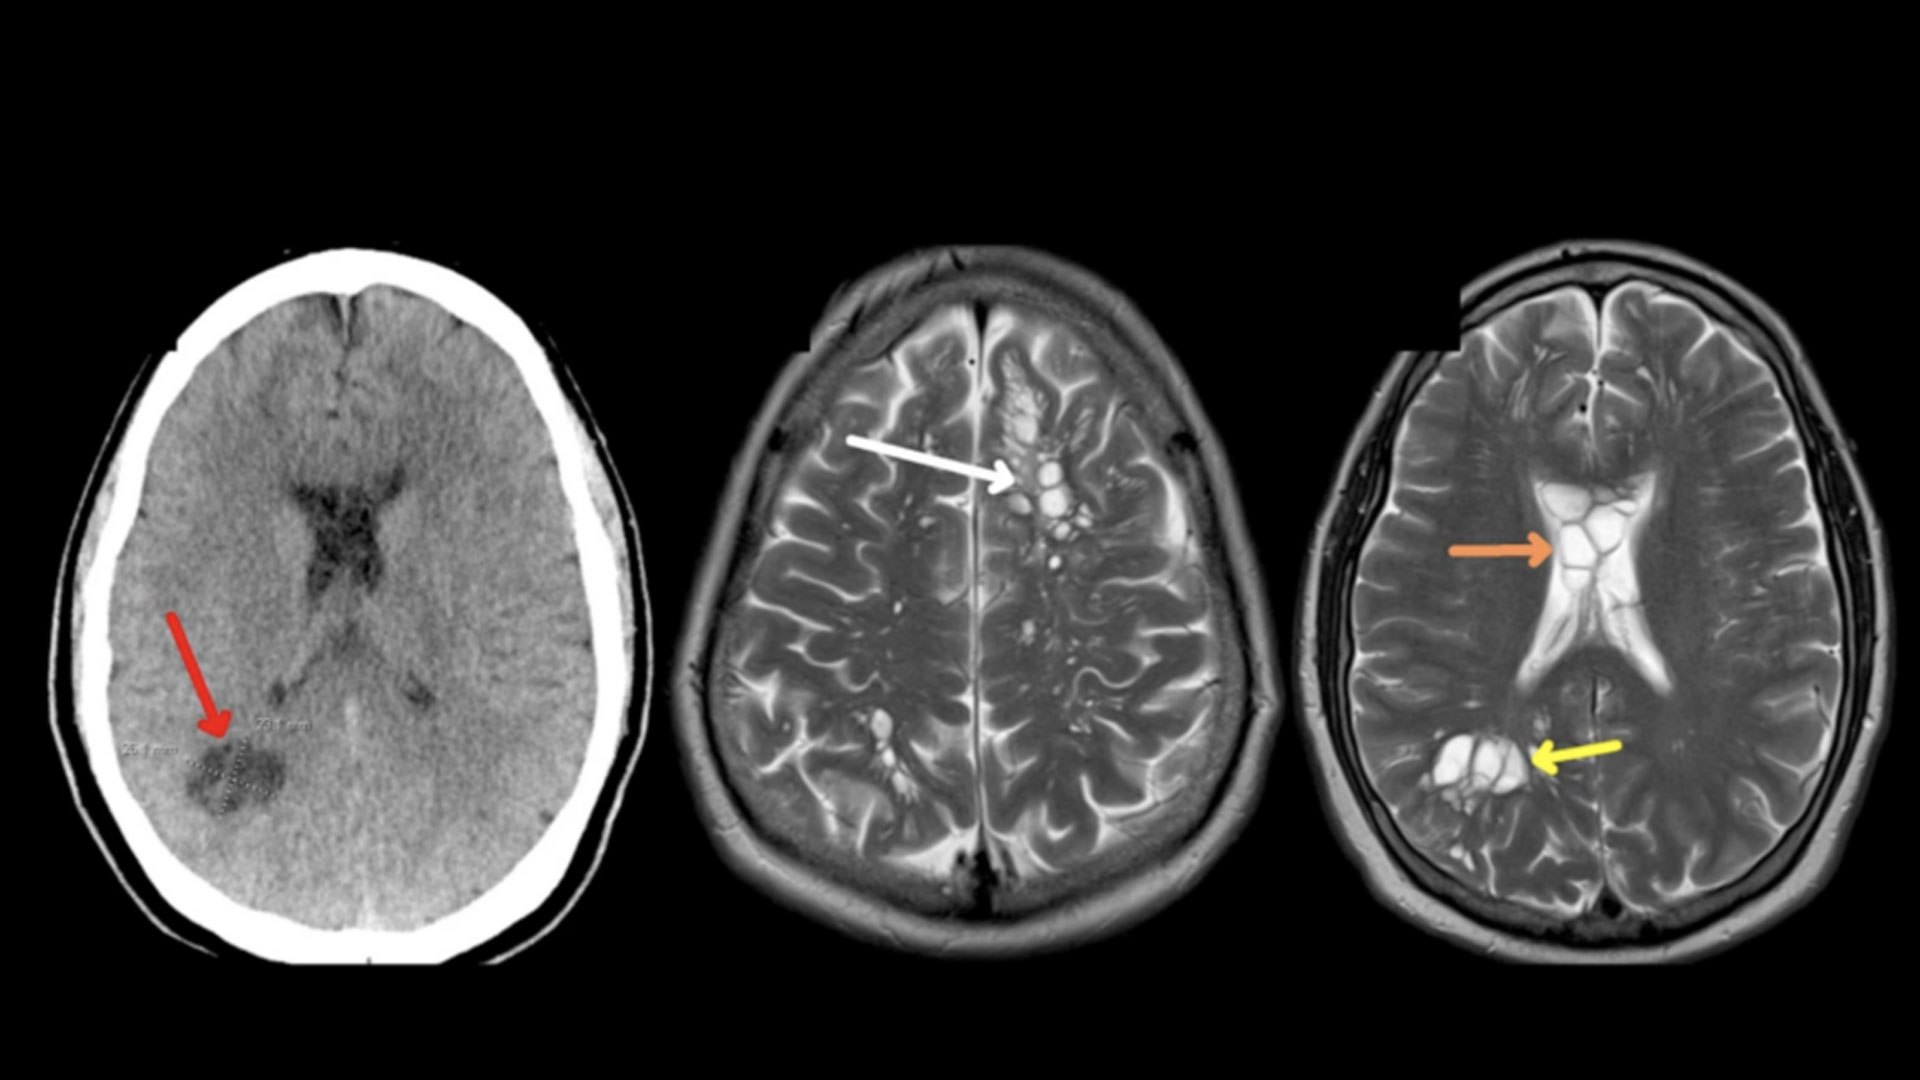

সবচেয়ে বেশি সমস্যা হয় যদি মস্তিষ্কে এই লার্ভা পৌঁছে যায়। একে বলা হয় নিউরোসিস্টিসার্কোসিস। মস্তিষ্কে সিস্ট হলে কনভালশান বা খিঁচুনি-তড়কা, হঠাৎ করে অজ্ঞান হওয়া ইত্যাদি সমস্যা দেখা দেয়। এই পর্যায়ে আক্রান্ত ব্যক্তি গুরুতর অসুস্থ হয়ে পড়তে পারেন।

মস্তিষ্কের কোনো অংশে এক বা একাধিক ফিতাকৃমির লার্ভার অবস্থানের ফলে সেরিব্রোস্পাইনাল ফ্লুয়িডের প্রবাহ ব্যাহত হয়। ধীরে ধীরে জায়গাটি ফুলতে শুরু করে। এতে কথা বলা, দেহের স্বাভাবিক চলাচল ব্যাহত হয়। অনেকক্ষেত্রে এই সমস্যায় অস্ত্রোপচারও করতে হয়। পাশাপাশি রেটিনার পিছনেও এই লার্ভা অবস্থান করতে পারে।